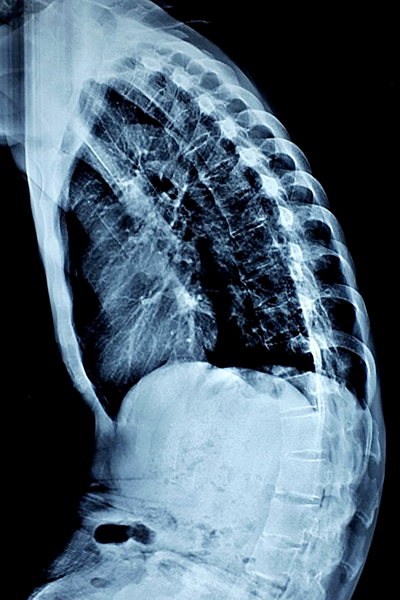

Ảnh chụp X-quang cột sống của bệnh nhân cong, gập trước khi phẫu thuật. Ảnh do bác sĩ cung cấp.

Các bác sĩ Bệnh viện Trung ương Quân đội 108 tiến hành nắn chỉnh biến dạng gù của chàng trai bằng kỹ thuật mới với 4 thanh rod thay vì 2 thanh như trước. Trong đó 2 thanh ngắn cố định từ đốt sống L2 đến L4, 2 thanh dài cố định từ đốt sống T10 đến S1. Kíp phẫu thuật đã cắt một phần đốt sống L3 để nắn chỉnh lại cột sống đã biến dạng.

Viêm cột sống dính khớp là bệnh lý viêm và cốt hóa các khớp, các dây chằng của cột sống. Gù cột sống là một trong những biến chứng nặng nề của bệnh. Phẫu thuật nắn chỉnh biến dạng gù do viêm cột sống dính khớp là một thách thức lớn của bác sĩ, do tình trạng cứng chắc của cột sống, khó tính toán mức độ biến dạng cần nắn chỉnh và vị trí can thiệp vào cột sống.